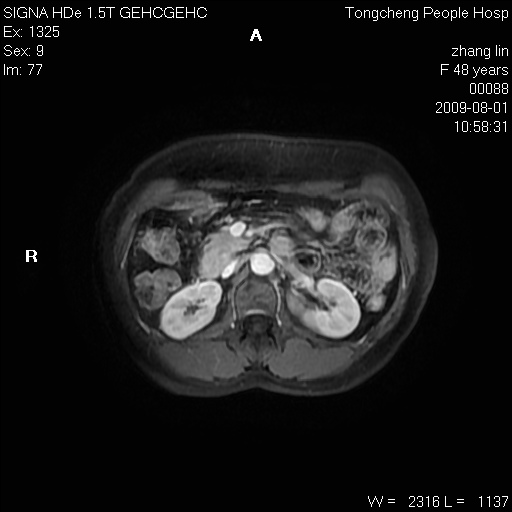

女,48岁。健康体检,彩超发现右肾占位性病变。平素健康。

临床诊断:右肾占位性病变,性质待定(囊肿?肿瘤?)。

上中腹部mr平扫+增强扫描,图像如下:

右肾上极见一类圆形病灶,t1wi呈等信号t2wi呈等高混杂信号,三期增强无强化,边界清---考虑囊肿出血。

同反相位均表现为等信号,病变无强化,考虑含蛋白的囊肿可能,弥散加权相或许有些帮助,

慢性胆囊炎